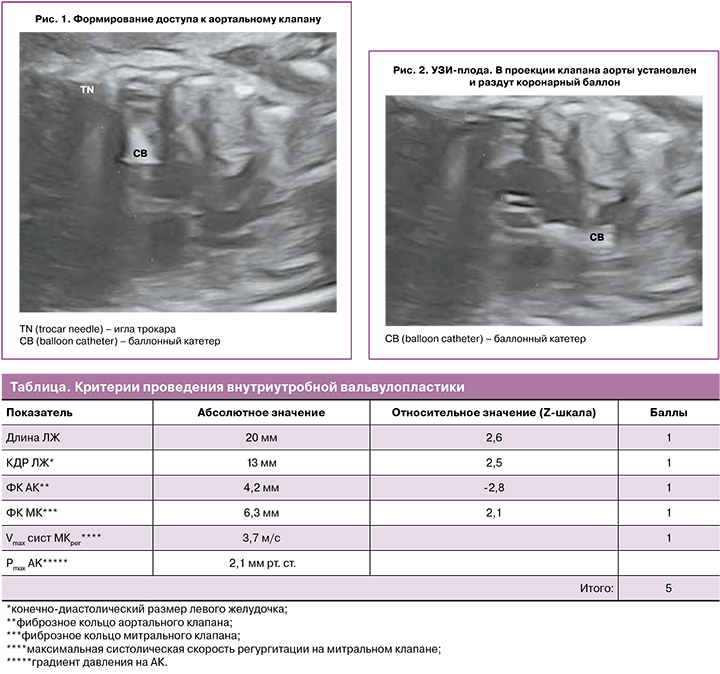

4. Предикторы возможности сохранения бивентрикулярного типа кровообращения, являющиеся накопительными, то есть должны присутствовать как минимум 4 из указанных в Международном регистре внутриутробных вмешательств на сердце плода, представлены в виде таблицы.

Под ультразвуковой навигацией иглой 18 G проведена пункция передней брюшной стенки беременной, игла продвинута через стенку матки до грудной клетки плода. Далее, через грудную клетку, игла введена в ЛЖ плода через его верхушку в направлении клапана аорты на 1/2 расстояния от верхушки ЛЖ до АК (рис. 1).

После извлечения мандрена заранее подготовленный комплекс проводник/баллон был введен через иглу и проведен в клапан аорты. Для предотвращения кровопотери на иглу был установлен Y-коннектор. Учитывая малый диаметр иглы, вальвулопластика производилась коронарным баллоном. Диаметр баллона подбирался аналогично тому, как это делается при вальвулопластике в постнатальном периоде: соотношение диаметра баллона и фиброзного кольца клапана аорты 1:1 [11]. В нашем случае был использован баллон диаметром 3,0 мм.

После заведения баллона с проводником в клапан аорты было произведено раздувание баллона (рис. 2).